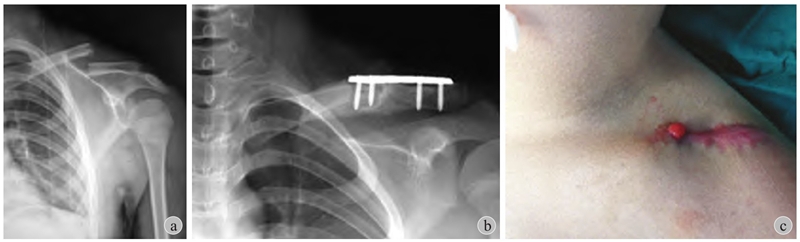

(2)锁骨骨折儿童期通常不需要切开复位内固定(图4)。在面对家长强烈的手术意愿下,应该与家长沟通选择合适的治疗方式,坚守儿童骨折的治疗原则。倘若因违背手术适应证而造成术后骨不连、骨髓炎等严重并发症,不仅患者的利益受到损害,更可能会引起诉讼纠纷。

图4 患儿,男,10岁

a:左锁骨骨折应考虑保守治疗;b:外院行切开复位+接骨板固定;c:术后发生感染及骨髓炎